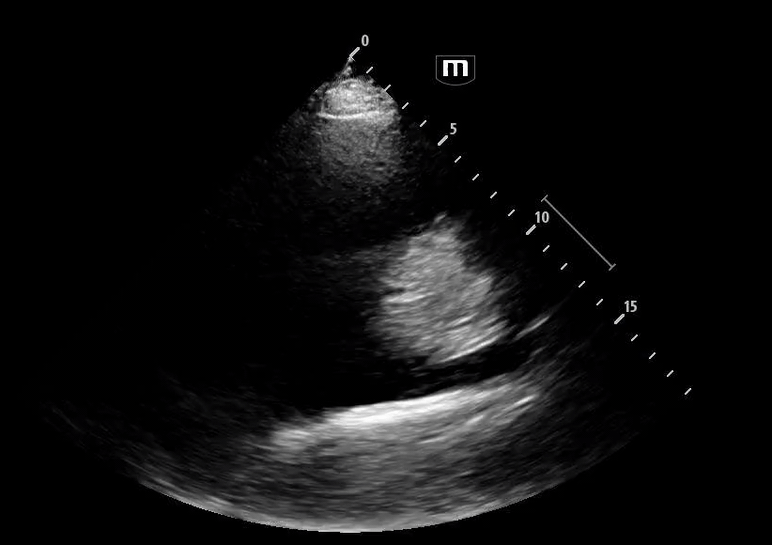

She isn’t crashing—but she isn’t stable either. Luckily, an ultrasound is immediately available. An eFAST exam is performed, revealing the following:

Image 1 demonstrates the left lung view with absence of lung sliding.